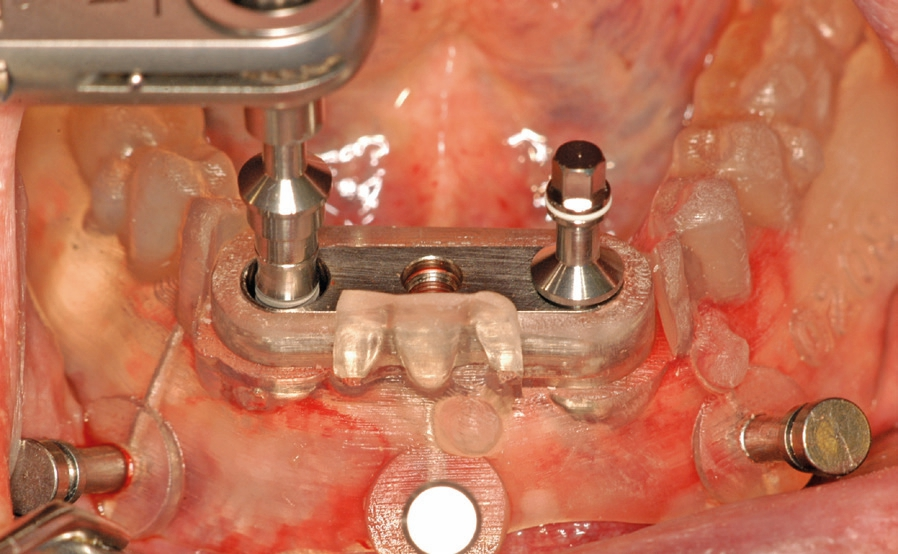

Abb. 13: Direkt nach der Implantation wird der Steg definitiv montiert und die Schrauben mit 30 N/cm festgezogen.